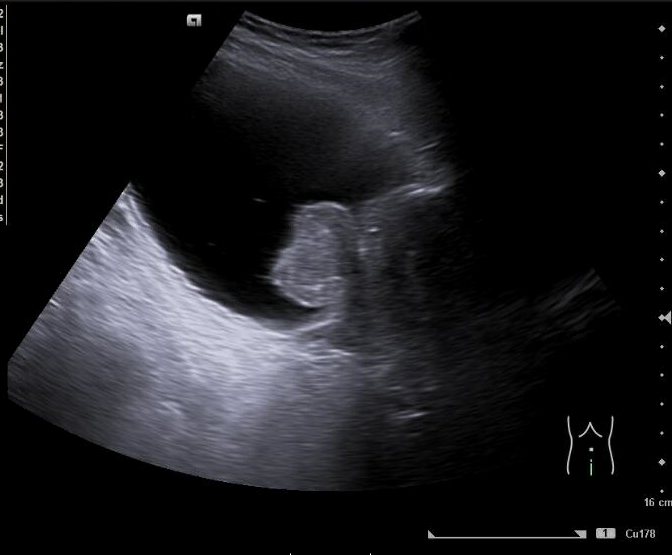

Imágenes 2 y 3. Riñón izquierdo: hidronefrosis grado II. Disminución del grosor cortical. Tamaño 11.5 cm.